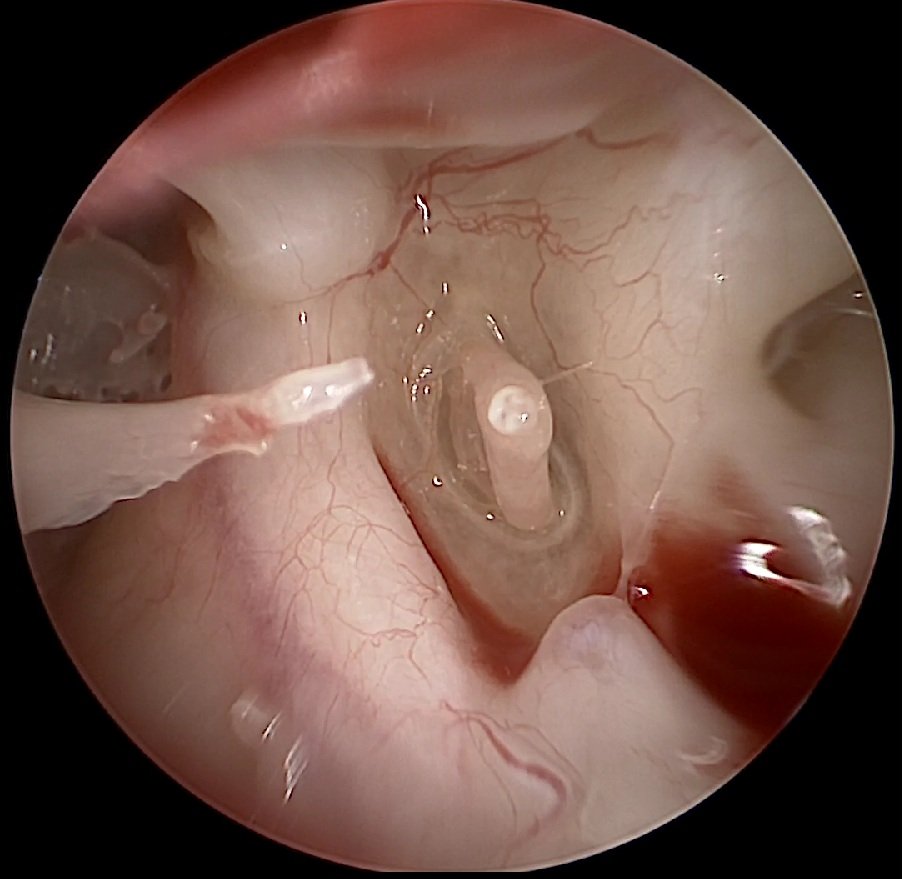

We begin with a full ear and hearing assessment. Using microscopy, audiometry, and nasal endoscopy, we confirm the cause of your symptoms and explain your treatment options.

Our ENT specialists tailor treatment to your needs. Mild cases may improve with the use of nasal sprays, decongestants, or balloon dilation. More complex cases may require minimally invasive surgery to restore ventilation and improve ear function.